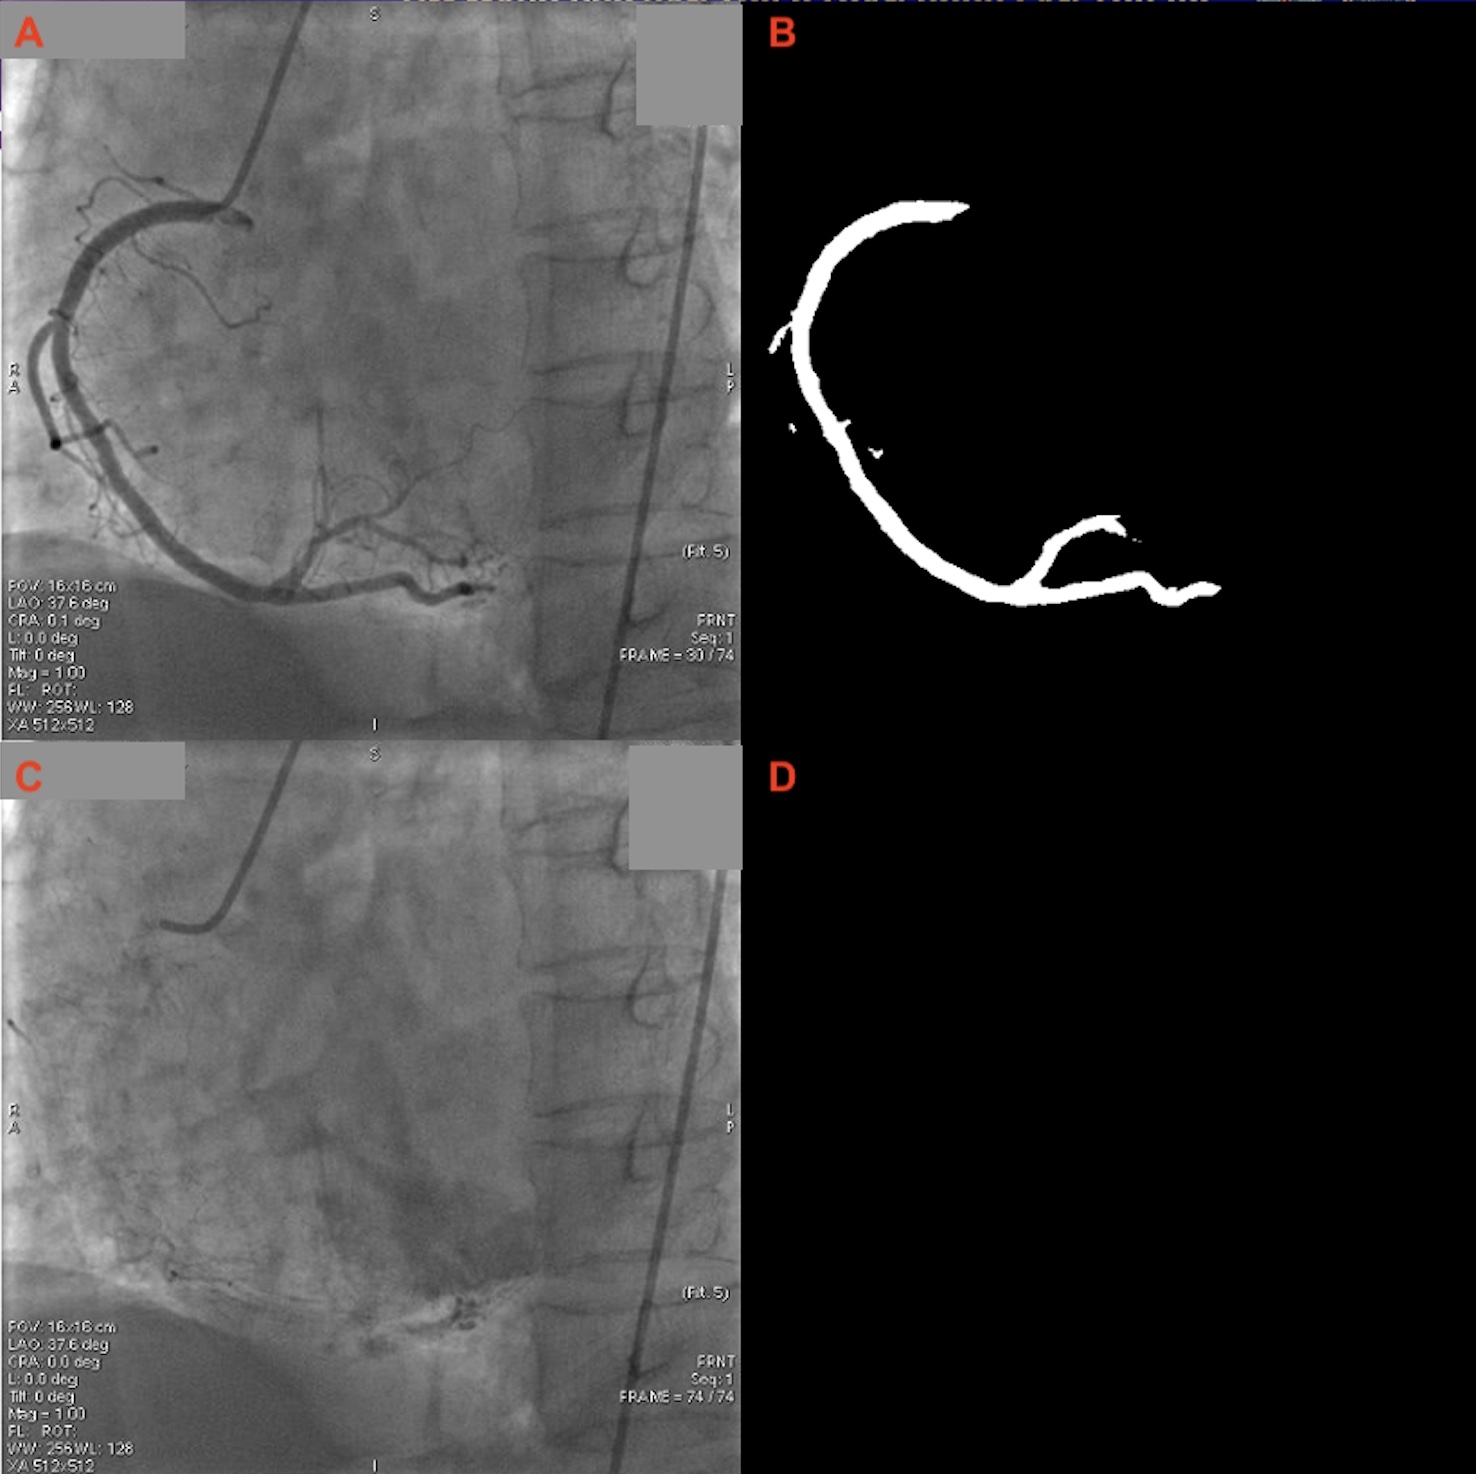

Quantifying the Coronary Artery Slow Flow Phenomenon: Insight from Dynamic Angiography and Deep Learning

All patients underwent the angiogram included, and the exclusive criteria were patients with heart failure, cardiomyopathy, congenital heart disease, valvular disease, and multivessel disease. The angiographic recording began with the injection of contrast into the coronary artery and continued with the white-colored blood moving until all the contrast had been washed out from the arteries. The review of coronary was 15 frames per second and focused on the white-colored blood flow against a black contrast background. The arterial phase (AP) calculation started when the blood began moving and ended when all the contrast was washed out of the distal arterial vasculature. The artificial intelligence program was built based on U-net and Densenet-121. At first, a segmentation model and a Convolutional neural network (CNN) model are responsible for detecting the starting frame of AP with a full index of contrast. In the end, the CNN model will detect the ending frame of AP.

151 patients met the inclusion criteria, and 76.8% were males. Subgroup analysis of patients with patent coronary arteries showed that the AP of the group with slow flow at the distal segment was 32.3 ± 4.4 frames. There was a statistically significant difference compared to the no-slow-flow group (p<0.001). The AP of patients with patent coronary artery was 25.8 ± 4.4 frames, compared with the AP of the group with a significant lesion, which was 32.2 ± 4.0 frames (p<0.001). The cut-off value of the AP frame count in diagnosing coronary slow flow was 27.5 frames, with a sensitivity of 91% and a specificity of 67%. Moreover, the Deep Learning model for calculating AP frames was successfully trained, achieving a root mean square error of 5.1 frames.